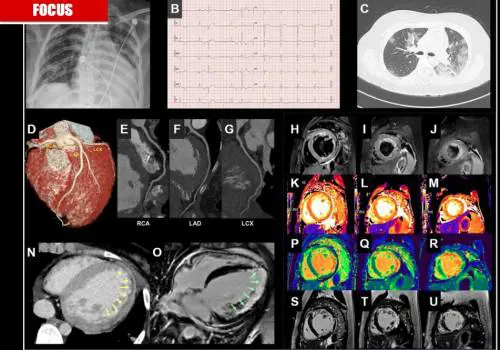

È possibile scoprire in tempo utile tre diversi profili di rischio per ictus e infarti su pazienti con l'aterosclerosi grazie al materiale genetico: ecco la scoperta e le implicazioni future